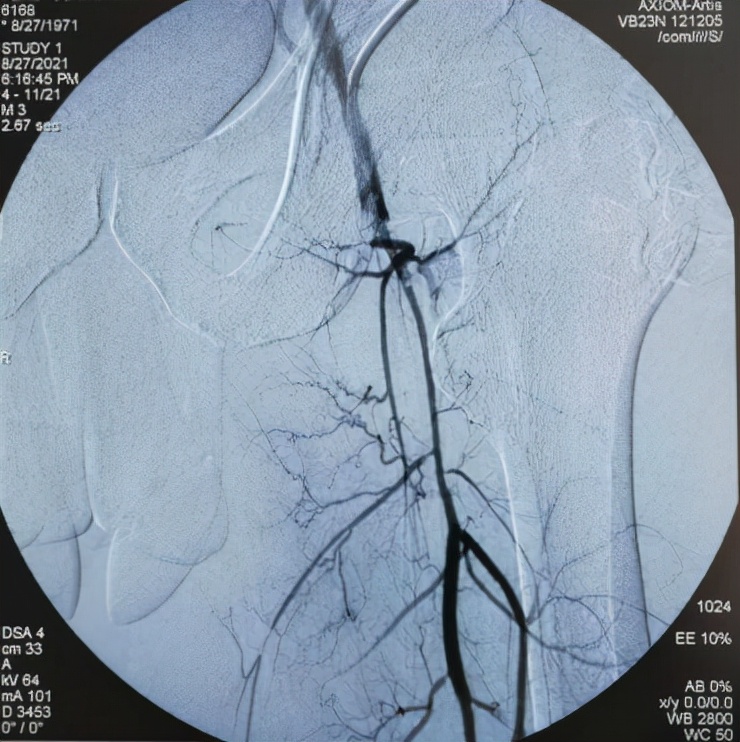

术后造影提示下肢主要血管和微血管已基本通畅

确切了解病情后,急诊科迅速联系血管微创介入科会诊并开通绿色通道。双下肢动脉CTA检查,较前对比左下肢血栓病情加重。介入科团队针对患者病情认真讨论后,与家属进行了充分沟通,决定行机械性血栓抽吸术。手术中给患者静脉抗凝药,经患侧股动脉造影了解血栓分布并确定治疗方案,连接高压注射器(器中含有溶栓药)在透视下将引导管移到股动脉、腘动脉的栓塞处,进行反复抽吸数次,直至膝上血管大部分开通。对于膝下部血栓也进行了反复抽吸,结束后进行造影显示股动脉、腘动脉、膝下动脉、足背部动脉血管通畅。